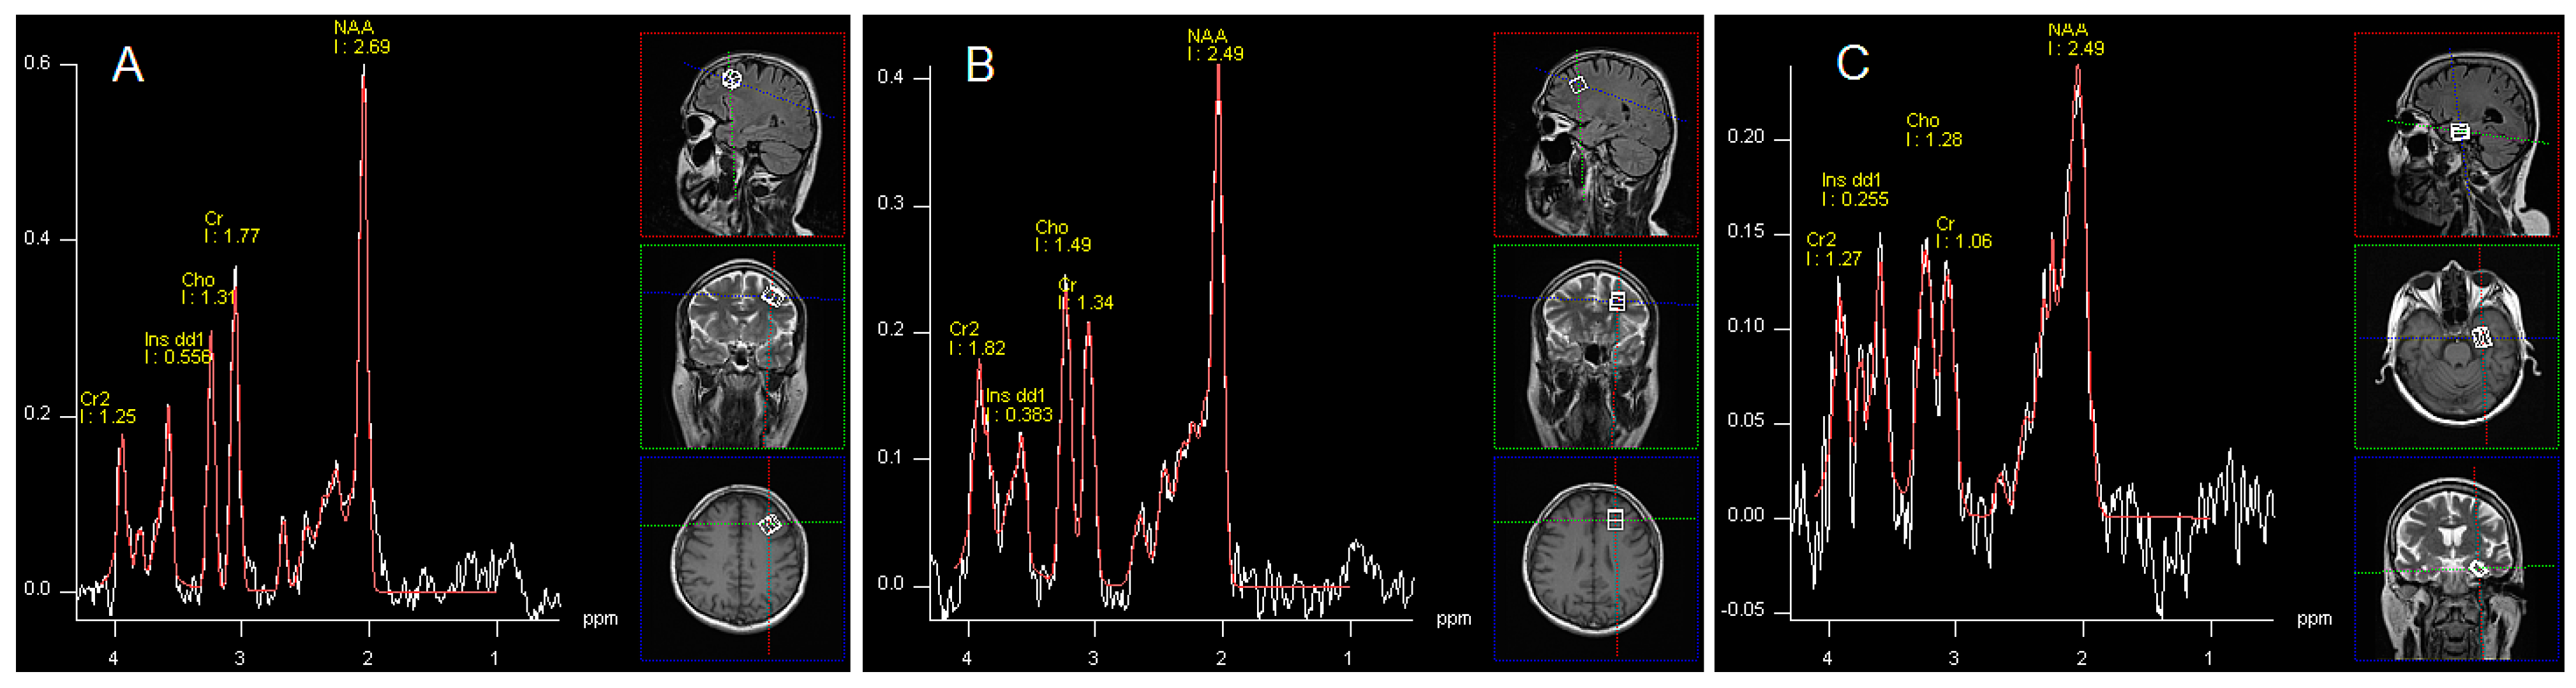

1H-MRS data were acquired by single voxel spectroscopy (SVS) using a point resolved spin echo (PRESS) sequence 128 averages; TR, 3000 ms; TE = 30 ms; voxel size was 15 × 15 × 15 mm for the left DLPFC, the left frontal WM and 10 × 15 × 20 mm for the left hippocampus. Regions of interest were placed in: the left DLPFC, left frontal WM and left hippocampus by a neuroradiologist (Figure 1). Automated procedures were used to optimize radiofrequency pulse power, field homogeneity, and water suppression, as well as to convert the lines into a Gaussian shape. Post-processing of spectroscopy data was performed by means of Avanto Syngo MR Software (Siemens, Munich, Germany), Level B15. It included: k-space Fourier transformation and a spatial 50 Hz Hanning filter; subtraction of the residual water signal; time domain 1 Hz exponential apodization; zero filling to 2048 points; Fourier transformation of the time domain signals; frequency shift correction, phase correction, and baseline correction. In postprocessing software also provided information about fitting error (deviation between theoretical and measured spectrum determined using the last squares method). We assumed that only spectra with fitting error less than 0.5 would be considered in the analysis. If the error was higher, the sequence was repeated. Hence, in all patients we received satisfactory values (mean fitting error 0.27 SD 0.12). The following metabolites were assessed: N-acetylaspartate (NAA); glutamine, glutamate and partially GABA (Glx); myo-inositol (mI); choline-containing compounds (Cho); creatine plus phosphocreatine (Cr). No absolute concentrations of metabolites were determined, but ratios to Cr and Cho.

Figure 1. Images showing voxel location in the left DLPFC area (A), left frontal WM (B), left (C) and an examples before (white line) and after (red line) fitting. Peak areas for N-acetylaspartate (NAA); creatine (Cr and Cr2); choline (Cho); and myo-inositol (mI dd1) are labelled.